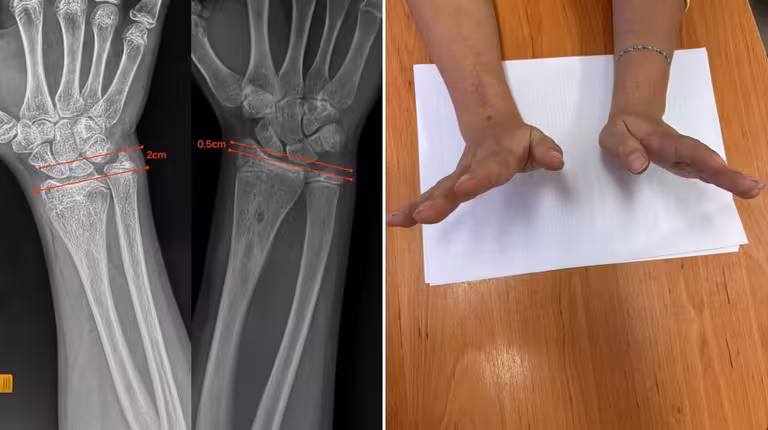

Обстеження показало, що ріст однієї з кісток був порушений через утворення кісткового містка, який блокував природний розвиток і спричиняв деформацію.

Під час операції лікарі видалили кістковий місток під контролем ендоскопа. Завдяки такому щадному методу вдалося обійтися без остеотомій та встановлення металоконструкцій — природний ріст кістки відновився самостійно.

Через сім місяців форма передпліччя повністю нормалізувалася, ріст кістки відбувається правильно, а функція кінцівки збережена у повному обсязі.